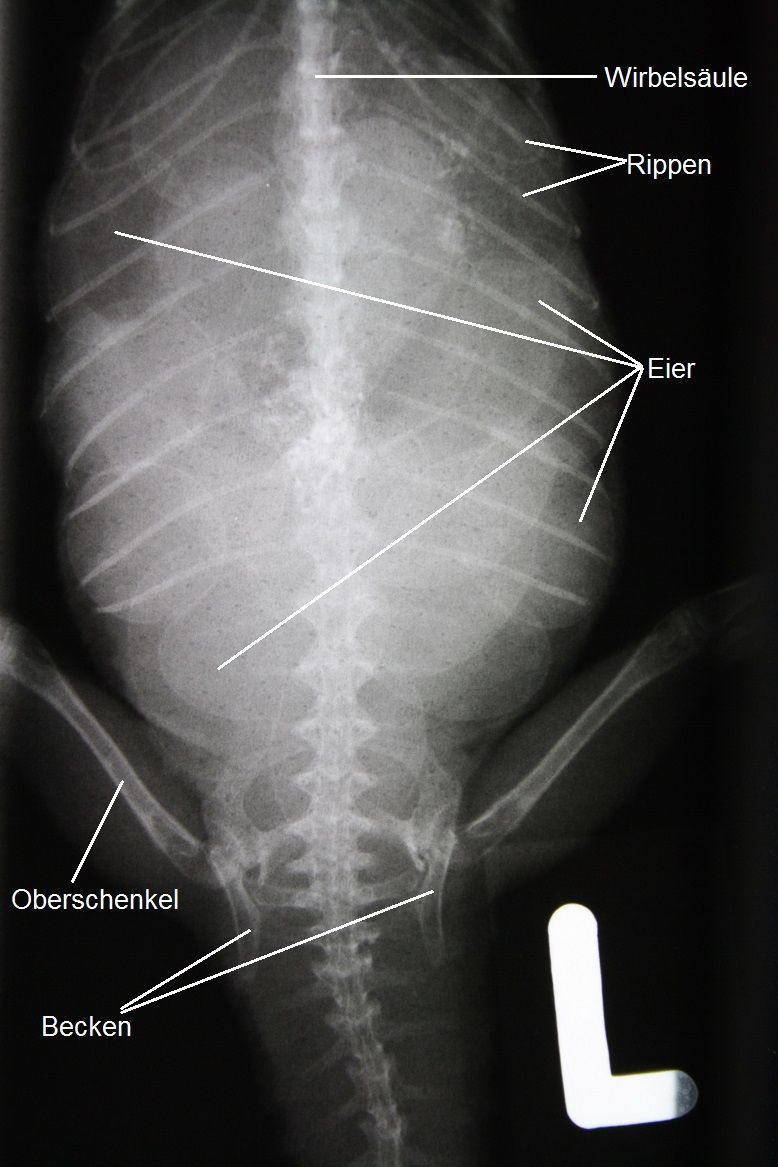

Der Bauch der Agamen-Dame kann problemlos untersucht werden; er erscheint etwas erweitert, und es lassen sich eine grössere Zahl gut erdnussgrosser Eier ertasten. Ein Röntgenbild bestätigt, dass sich rund ein Dutzend Eier im Legedarm des Tieres befinden.